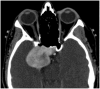

Intracranial trigeminal schwannomas are rare tumors. Patients usually present with symptoms of trigeminal nerve dysfunction, the most common symptom being facial pain. MRI is the imaging modality of choice and is usually diagnostic in the appropriate clinical setting. The thin T2-weighted CISS 3D axial sequence is important for proper assessment of the cisternal segment of the nerve. They are usually hypointense on T1, hyperintense on T2 with avid enhancement post gadolinium. CT scan is supplementary to MRI, particularly for tumors located in the skull base. Imaging plays a role in diagnosis and surgical planning. In this pictorial essay, we retrospectively reviewed imaging findings in nine patients with pathologically proven trigeminal schwannoma. Familiarity with the imaging findings of intracranial trigeminal schwannoma may help to diagnose this entity.